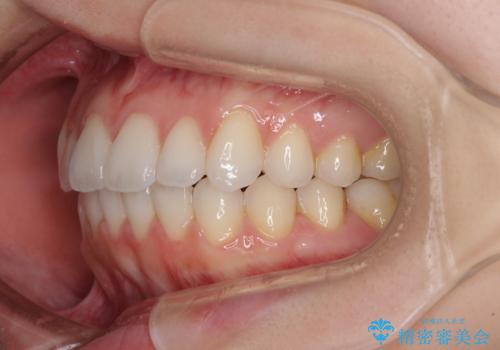

インビザライン・ライトにより後戻りの再矯正

- インビザライン・ライト

- 治療期間

- 9ヶ月

舌突出癖の改善により上下前歯が接触するようになり、前歯でものを咬みきる必要のある食事がスムーズに行えるようになりました。